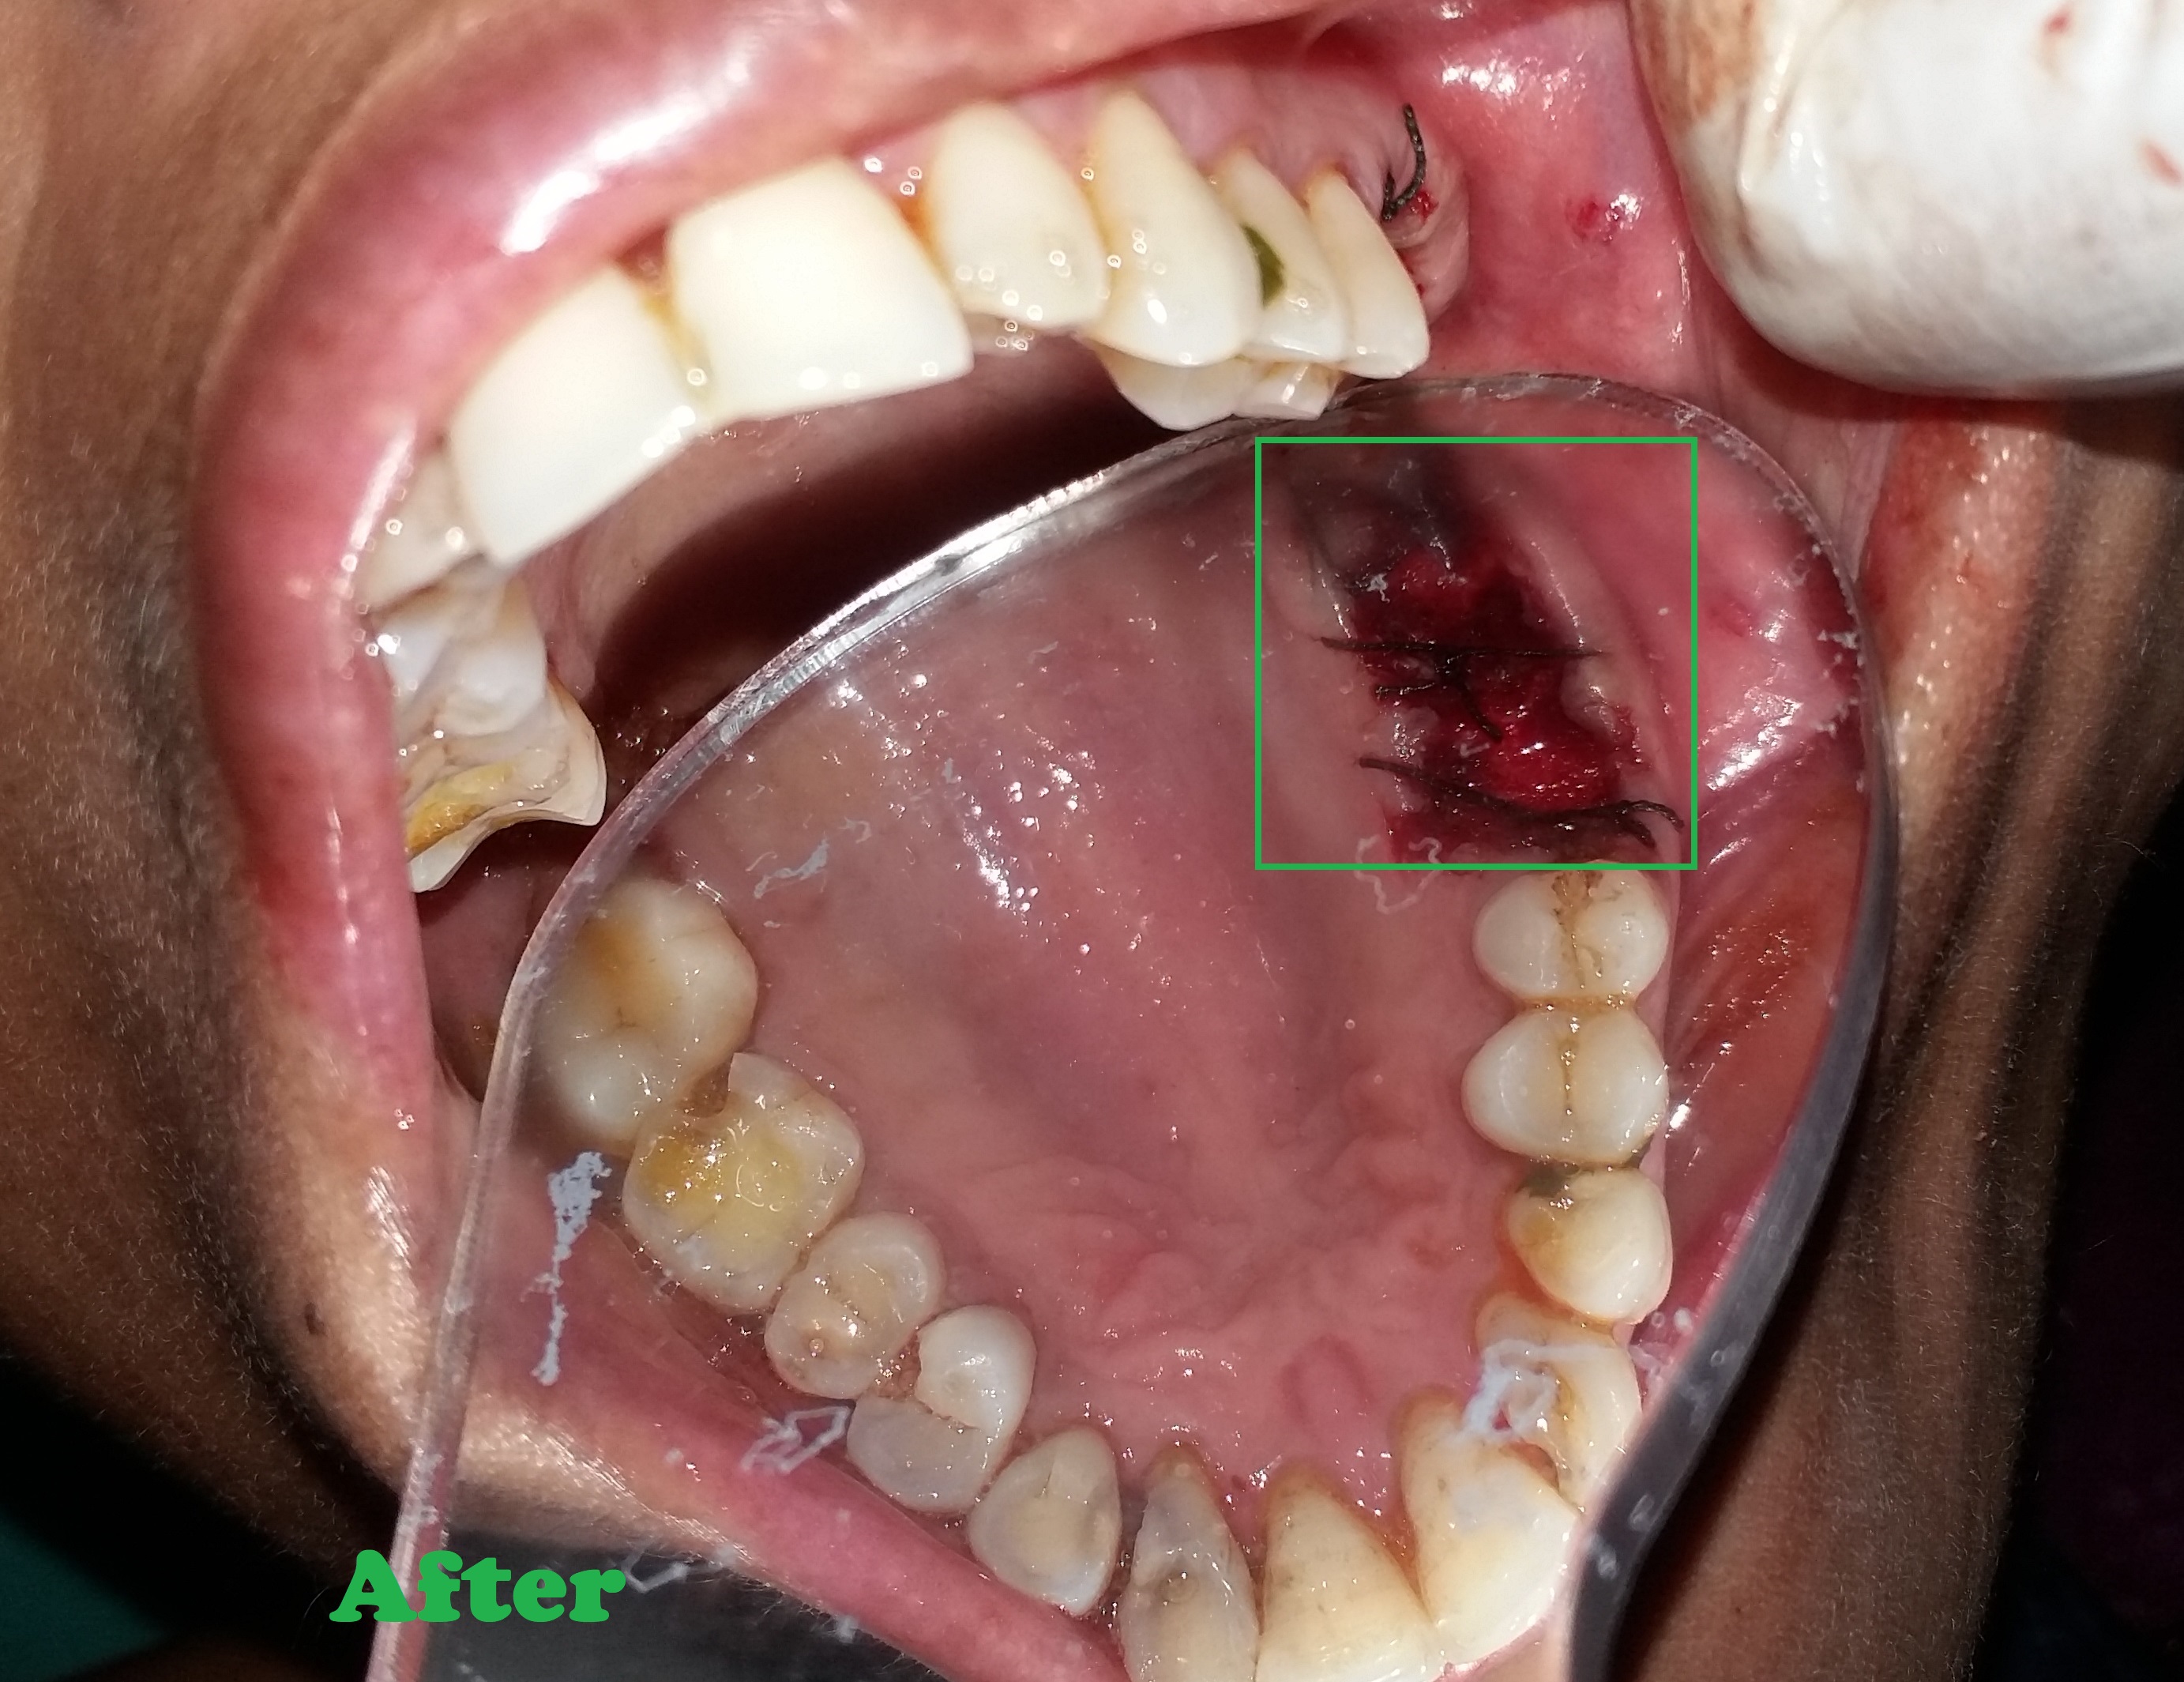

- Removes infected nerve tissue while preserving your natural tooth.

- Relieves pain, swelling, and sensitivity caused by deep decay or infection.

- Protects against tooth extraction and maintains natural biting ability.